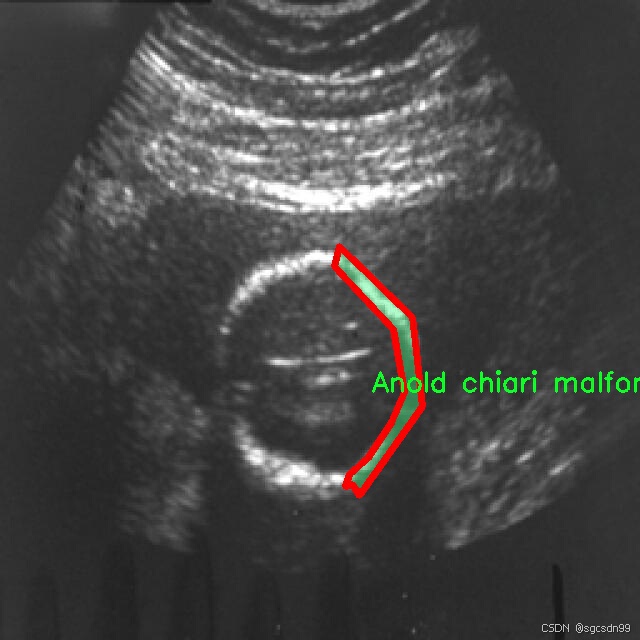

2.图片演示

names: [‘Anold chiari malformation’, ‘Arachnoid cyst’, ‘Cerebellah hypoplasia’, ‘Cisterna magna’, ‘Colphocephaly’, ‘Encephalocele’, ‘Holoprosencephaly’, ‘Hydracenphaly’, ‘Intracranial hemorrdge’, ‘Intracranial tumor’, ‘Mild ventriculomegaly’, ‘Moderate ventriculomegaly’, ‘Polencephaly’, ‘Severe ventriculomegaly’]

在现代医学影像学中,胎儿脑部异常的早期识别对于提高临床干预的有效性至关重要。为此,本研究利用名为“mask-rcnn-detectron2”的数据集,旨在训练一种改进的YOLOv8-seg图像分割系统,以实现对胎儿脑部异常的高效识别和分割。该数据集包含14个类别,涵盖了多种常见的胎儿脑部异常,具体类别包括:Anold chiari malformation(阿诺德-基亚里畸形)、Arachnoid cyst(蛛网膜囊肿)、Cerebellah hypoplasia(小脑发育不良)、Cisterna magna(大脑池)、Colphocephaly(脑室扩张)、Encephalocele(脑膨出)、Holoprosencephaly(全前脑发育不良)、Hydracenphaly(水脑)、Intracranial hemorrhage(颅内出血)、Intracranial tumor(颅内肿瘤)、Mild ventriculomegaly(轻度脑室扩大)、Moderate ventriculomegaly(中度脑室扩大)、Polencephaly(多脑半球发育)、Severe ventriculomegaly(重度脑室扩大)。

该数据集的丰富性和多样性为训练深度学习模型提供了坚实的基础。每个类别都代表了一种特定的胎儿脑部异常,这些异常在临床上具有重要的诊断意义。通过对这些类别的细致标注,研究人员能够训练出更为精准的模型,从而在实际应用中提高识别的准确性和效率。例如,阿诺德-基亚里畸形和全前脑发育不良是两种严重的脑部异常,及时的识别可以为后续的治疗方案提供重要依据。